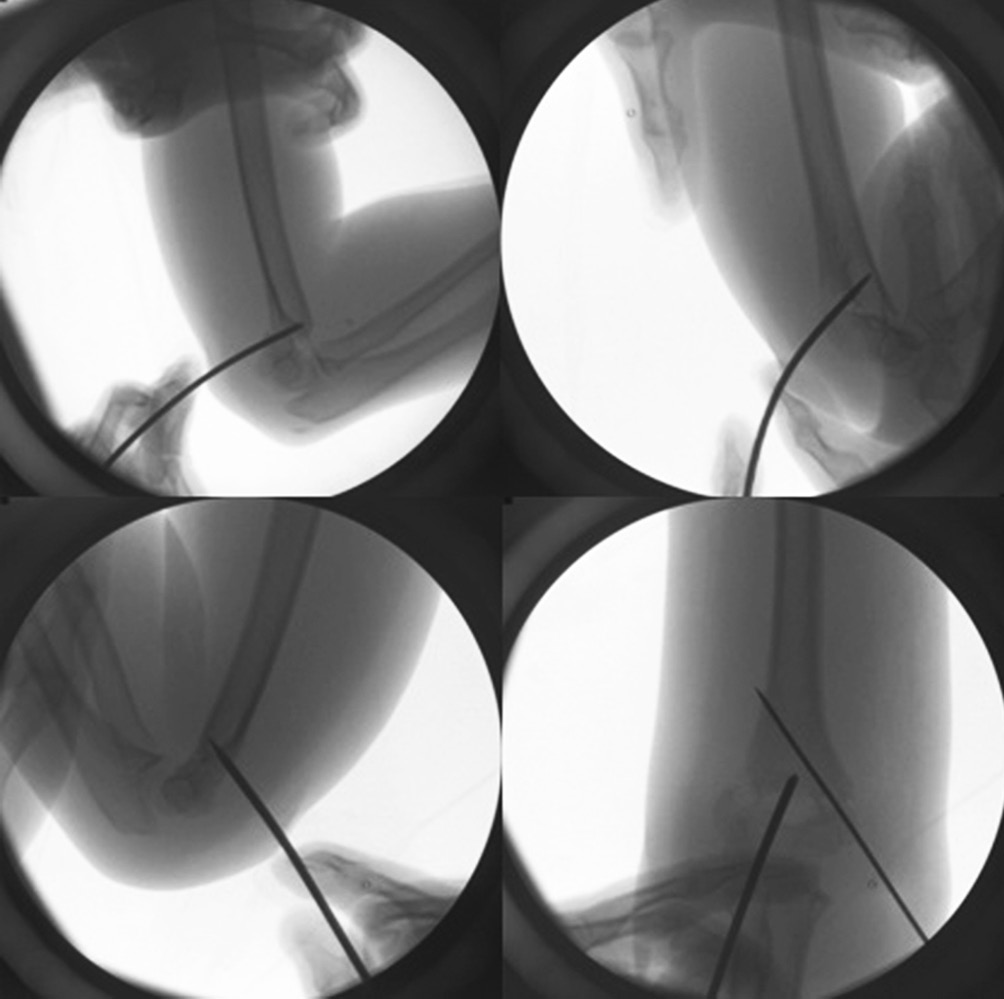

The surgery was performed by a single surgeon. General anesthesia was used for all cases. Tourniquet was not used in any case. Surgical procedure included closed reduction and percutaneous pin fixation under general anesthesia. If the closed reduction failed or reduction state was not satisfactory, additional reduction was achieved by joystick maneuver using 2.4 mm K-wire (Fig. 1). After reduction, 1.4 mm or 1.6 mm K-wires were used to fix fractures. At postoperative 3 weeks, radiographs were evaluated and the timings for pin removal and cast removal were decided according to the status of fracture healing. After removal of the pin and cast, patients started daily activities and tolerable exercise without passive physical therapy. Follow-up radiography was performed at 6 weeks, 3, 6, and 12 months.

Fig. 1. Reduction technique (joystick maneuver) using 2.4 mm K-wire